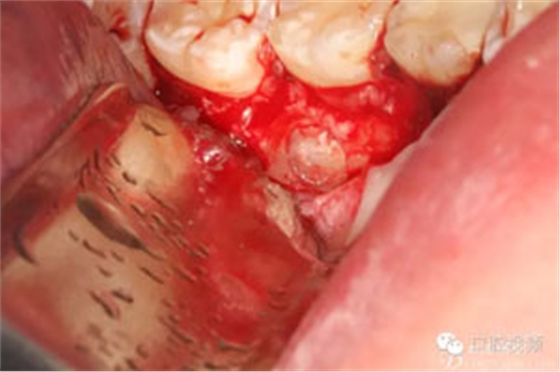

圖8.繼續(xù)去骨、暴露整個35牙冠。注意牽拉力度。